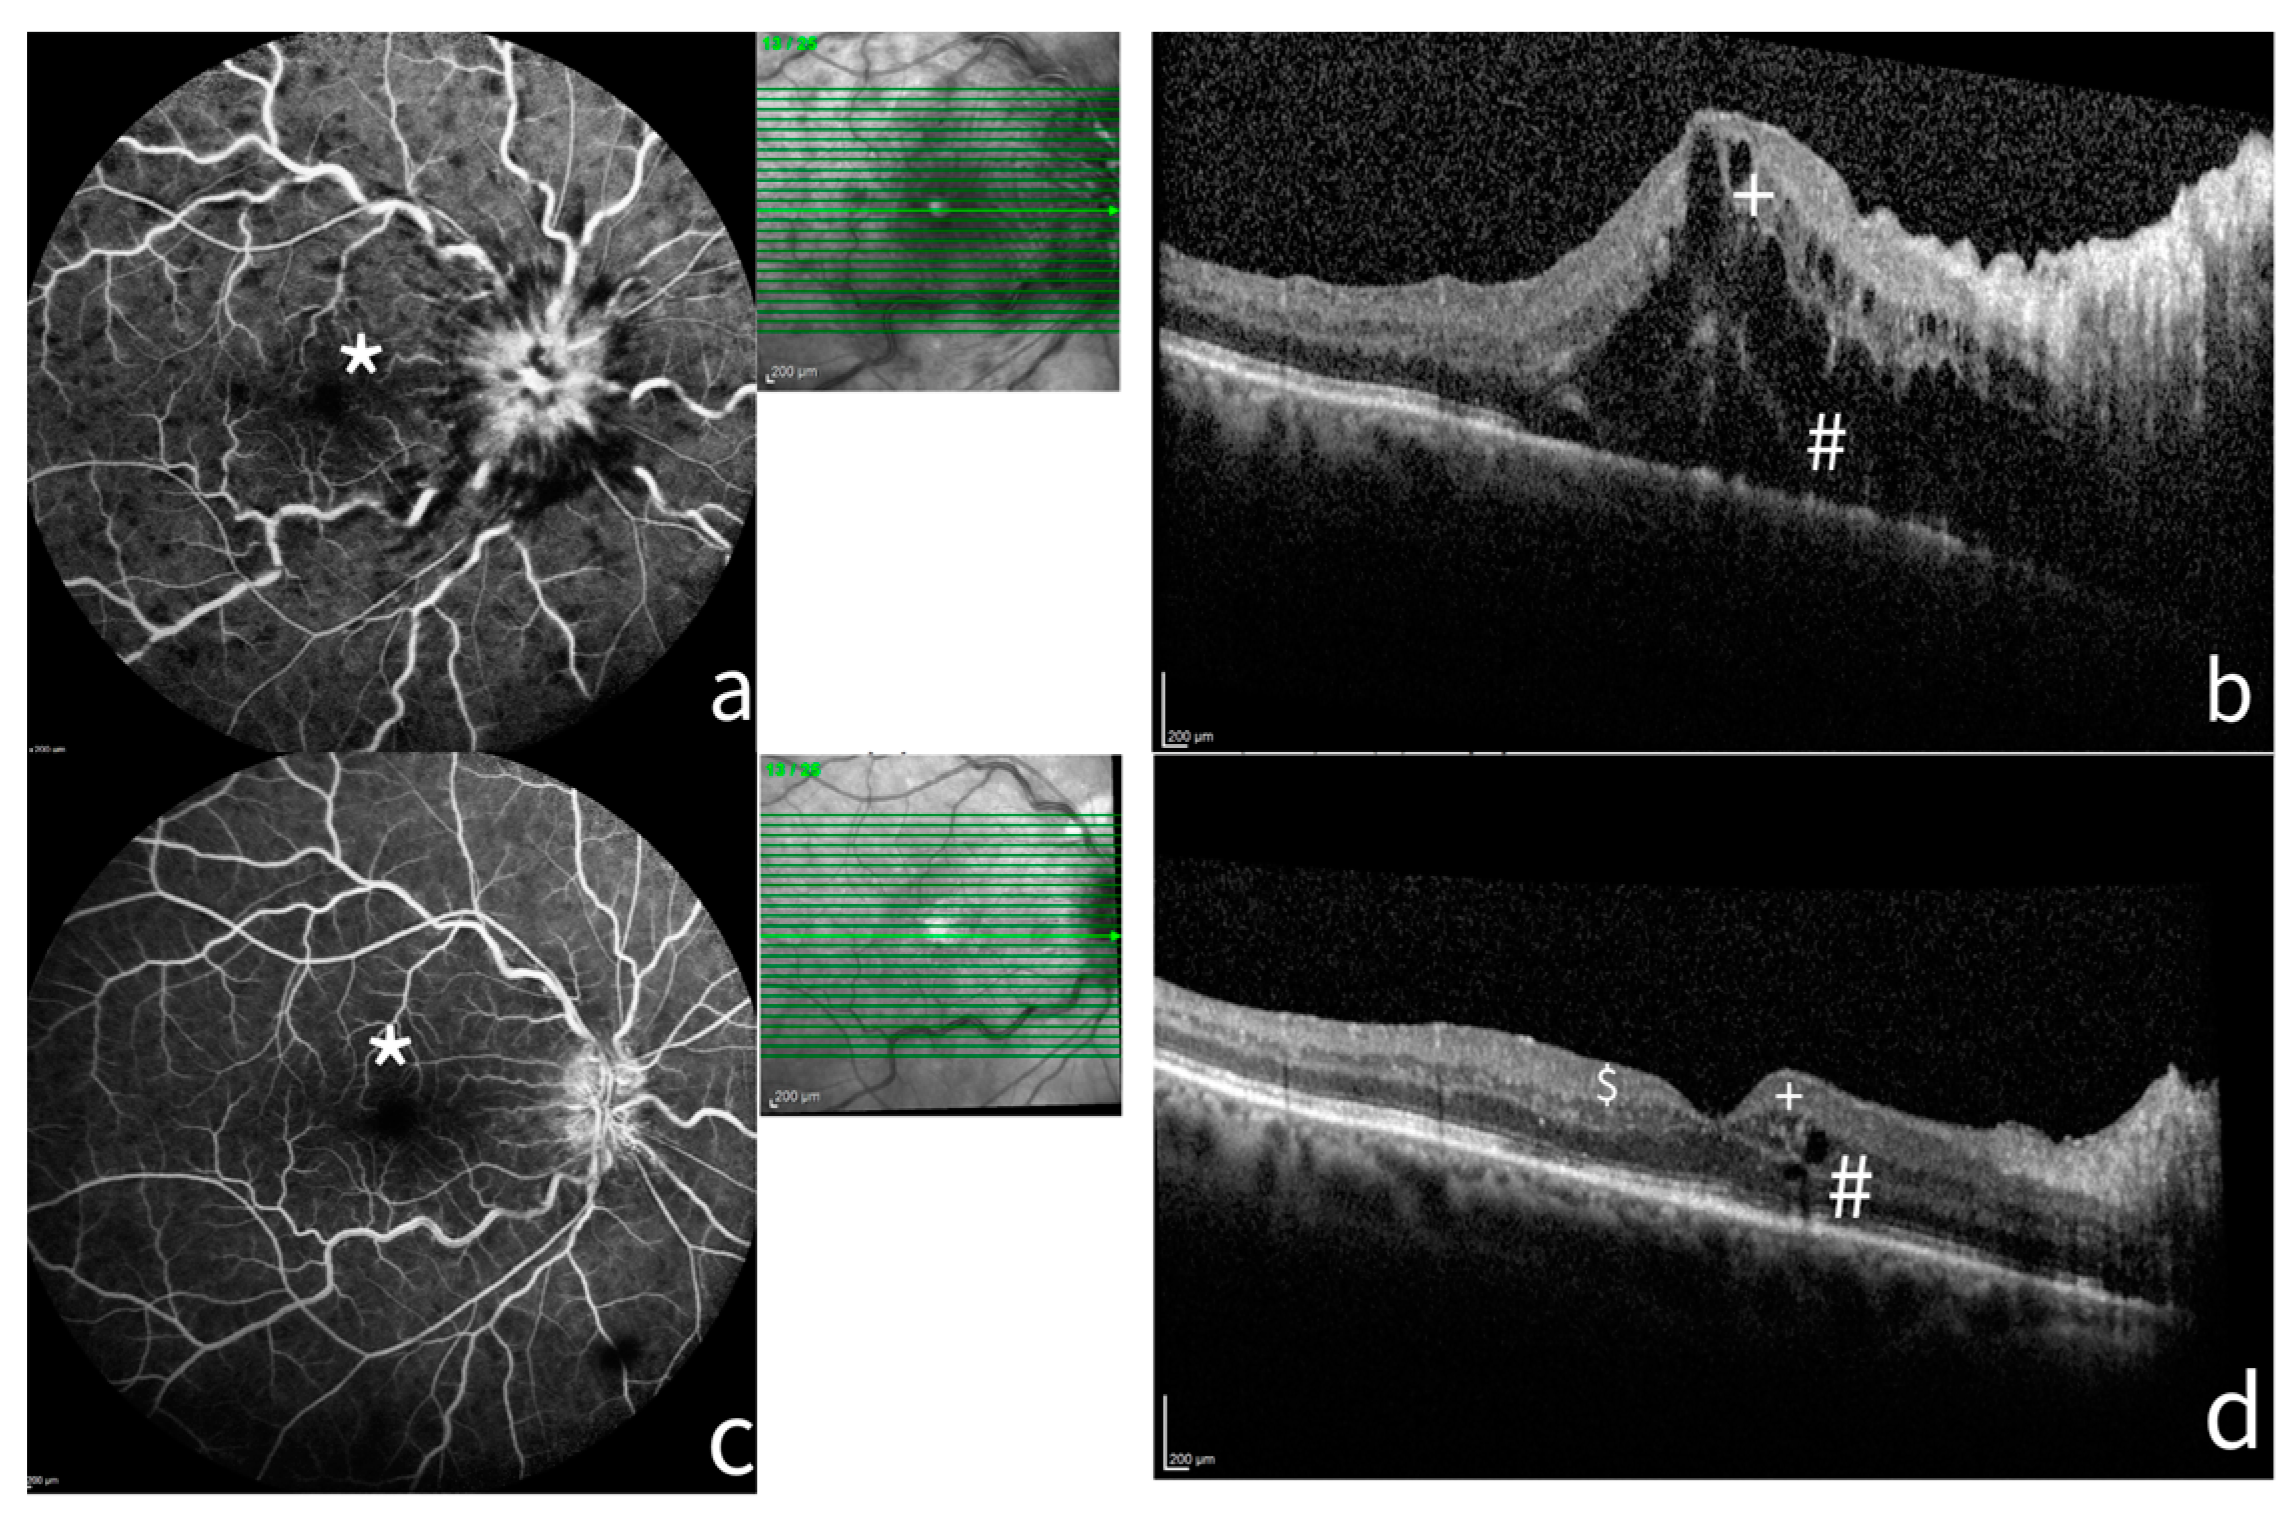

Disruptions of photoreceptors’ layers showed a significant association with visual outcome as well as the absence of macular ischemia at baseline and the branch type of RVO at twelve months (p < 0.05). Figure 1 shows a case of CRVO at baseline and at six months after treatment.

Figure 1.

A case of CRVO at baseline and six months after treatment. FA and SD-OCT of a patient before and after treatment. (a) FA shows a non-ischemic (*) central retinal vein occlusion (CRVO) with marked delay in arteriovenous transit time, masked by retinal haemorrhages, and vessel wall staining. (b) The SD-OCT shows ME with considerable central thickness, absence of DRIL (+), and incomplete disruption of ELM and EZ. (c) After six months of treatment, FA shows resolution of the RVO with late staining of optic disc. (d) The SD-OCT highlights the reduction in retinal thickness, the presence of HRF ($), resolution of photoreceptor layers (#), and absence of DRIL (+). FA: Fluorescein angiograms; SD-OCT: spectral domain–optical coherence tomography; ME: macula edema; DRIL: disorganization of retinal inner layers; ELM: external limiting membrane disruption; HRF: hyperreflective foci; EZD: ellipsoid zone disruption.